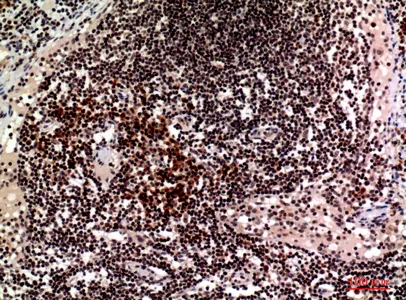

CD244 Rabbit Polyclonal Antibody

Cat: APRab08306

Size1:50μl Price1:$118

Size2:100μl Price2:$220

Size3:500μl Price3:$980

Size2:100μl Price2:$220

Size3:500μl Price3:$980